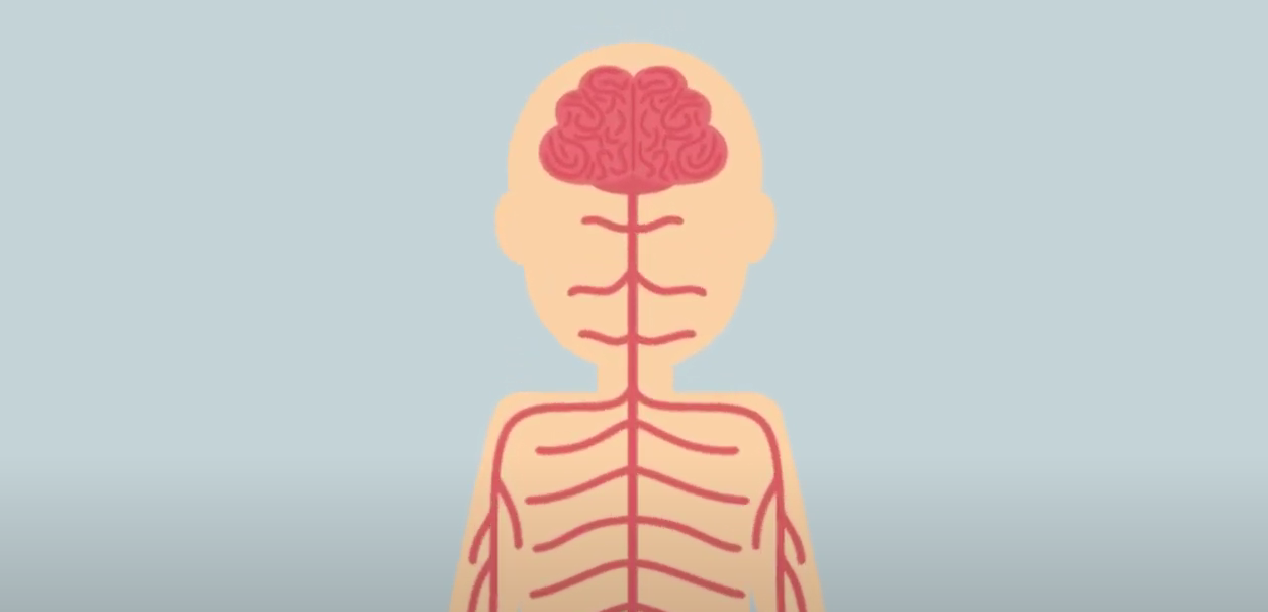

횡경막을 자극하는

'미주신경'에 더 강한 자극을 주면 되는데요.

미주신경이 자극을 받으면

이 자극이 딸국질보다 중요하다고

뇌에 신호를 보내고

뇌가 새로운 자극에 집중하면

딸국질이 멈추게 됩니다.